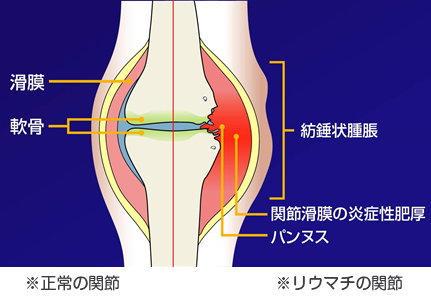

人間の体には外から侵入してくる細菌・ウイルスを退治するために免疫細胞があります。

その免疫細胞が間違って自分の体を攻撃してしまう病気をまとめて「膠原病」といいます。

どんな種類の免疫細胞が、体のどこを攻撃してしまうかによって症状が変わり、病気の名前も変わってきます。例えば涙腺や唾液腺を免疫細胞が攻撃してしまうと、目や口が乾いてしまうシェーグレン症候群という病気を起こしてきます、皮膚や筋肉を免疫細胞が攻撃すると皮膚にカサカサした発疹や筋力低下が起きる皮膚筋炎という病気が出てきます。膠原病の中にも、いろいろな種類の病気があるんですね。

その中で、関節リウマチは免疫細胞が自分の関節を攻撃してしまう病気です。

「朝のこわばり」、「手指の痛み・腫れ」が有名ですが、その他にも「肘」「膝」「足」「肩」など多くの関節に痛み・腫れが出てきます。またその状態を我慢してしまうと、関節の骨や腱が壊れてしまい、関節の変形を起こしてしまいます。

以前は有効な治療薬がなく、「痛み止め」や「ステロイドホルモン剤」で痛みを和らげることしかできず、多くの患者さんが痛みを完全に良くできないばかりか、リウマチの進行が止められずに手指が曲がり、肘・膝が脱臼したりして整形外科で手術をされたり、残念ながら寝たきりの状態になってしまっていました。

しかしここ10年で「生物学的製剤」ができたことで、リウマチの痛みをとるだけでなく、関節で悪さしている免疫細胞を落ち着かせて骨の破壊や関節変形を起こさない治療ができるようになりました。生物学的製剤の中には、妊娠・授乳中も使用できる薬もあり、今まで妊娠中はステロイドホルモン剤が中心であった治療も大きく変わっています。